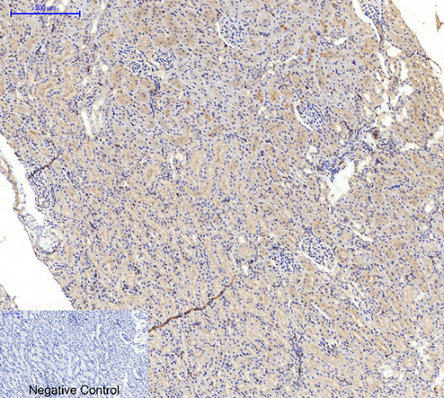

Immunohistochemical analysis of paraffin-embedded Rat-kidney tissue. 1,Actin β Polyclonal Antibody was diluted at 1:200(4°C,overnight). 2, Sodium citrate pH 6.0 was used for antibody retrieval(>98°C,20min). 3,Secondary antibody was diluted at 1:200(room tempeRature, 30min). Negative control was used by secondary antibody only. |